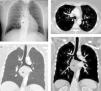

A) Radiografía de tórax en la que se observa una masa mediastínica (asterisco) que oblitera la línea pleuro-ácigos-esofágica y un posible bronquio traqueal (flechas). B) Reconstrucción coronal minIP (proyección de mínima intensidad) que confirma la existencia del bronquio traqueal. Nótese la masa mediastínica (asterisco). C) Imagen axial de TC de tórax con contraste intravenoso en la que se visualiza un drenaje anómalo de la vena pulmonar del lóbulo superior derecho en la vena cava superior (flechas) y el bronquio traqueal (cabeza de flecha). D) Imagen coronal oblicua de TC de tórax con contraste intravenoso en la que se aprecia el bronquio traqueal (flecha) y la masa mediastínica (asterisco).

Presentamos el caso clínico de una mujer de 45 años diagnosticada de NF1, no fumadora, que presentaba una disfagia secundaria a un tumor mediastínico posterior que comprimía el esófago torácico, compatible radiológicamente (mediante resonancia magnética) con un tumor neurogénico dependiente del nervio vago derecho. En la exploración física únicamente destacaban manchas «café con leche» en la superficie cutánea y varias cicatrices en la espalda y pared abdominal en relación con resecciones previas de neurofibromas en dichas localizaciones. Dada la sintomatología de disfagia progresiva se decidió intervenir quirúrgicamente a la paciente del tumor mediastínico posterior. En la radiografía de tórax preoperatoria (fig. 1A) se observó un posible bronquio traqueal (BT), por lo que se decidió completar dichos estudios con una tomografía computarizada (TC) de tórax, confirmándose la existencia del BT y su asociación inesperada con un drenaje venoso pulmonar anómalo parcial (DVPAP). El DVPAP consistía en un drenaje de la vena del lóbulo superior derecho en la vena cava superior (fig. 1B-D).